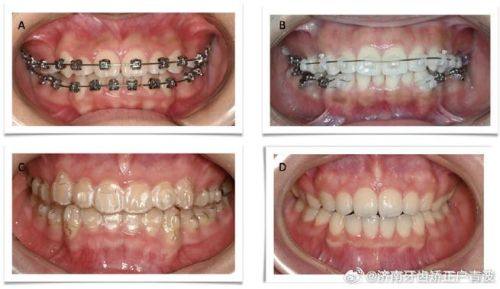

牙齿正畸:由专精正畸医生坐诊,提供科学化系统诊疗方案,兼顾科学、艺术与自然的治疗成效,帮助患者改善牙齿排列问题。

王超然:专注牙齿正畸领域,以患者为导向制定个性化正畸方案,提供科学化系统诊疗服务,兼顾科学、艺术与自然的治疗成效,注重学术交流,技术专精贴心,深受患者认可。

微笑青澄口腔门诊部 金属托槽牙齿矫正:7000元起

微笑青澄口腔门诊部 隐形牙齿矫正:12000元起

王女士做金属托槽矫正

"我因为牙齿不齐想做矫正,朋友推荐了微笑青澄的王超然医生。第一次面诊时,王医生特别专精,给我制定了个性化的矫正方案,详细讲解了矫正过程和费用,没有隐藏消费。矫正过程中,医生定期跟进我的情况,调整托槽,每次都特别耐心解答我的疑问。医院环境整洁,医护人员态度友好,现在矫正快半年了,牙齿已经有明显变化,真的特别感谢王医生,也推荐给有矫正需求的朋友。"